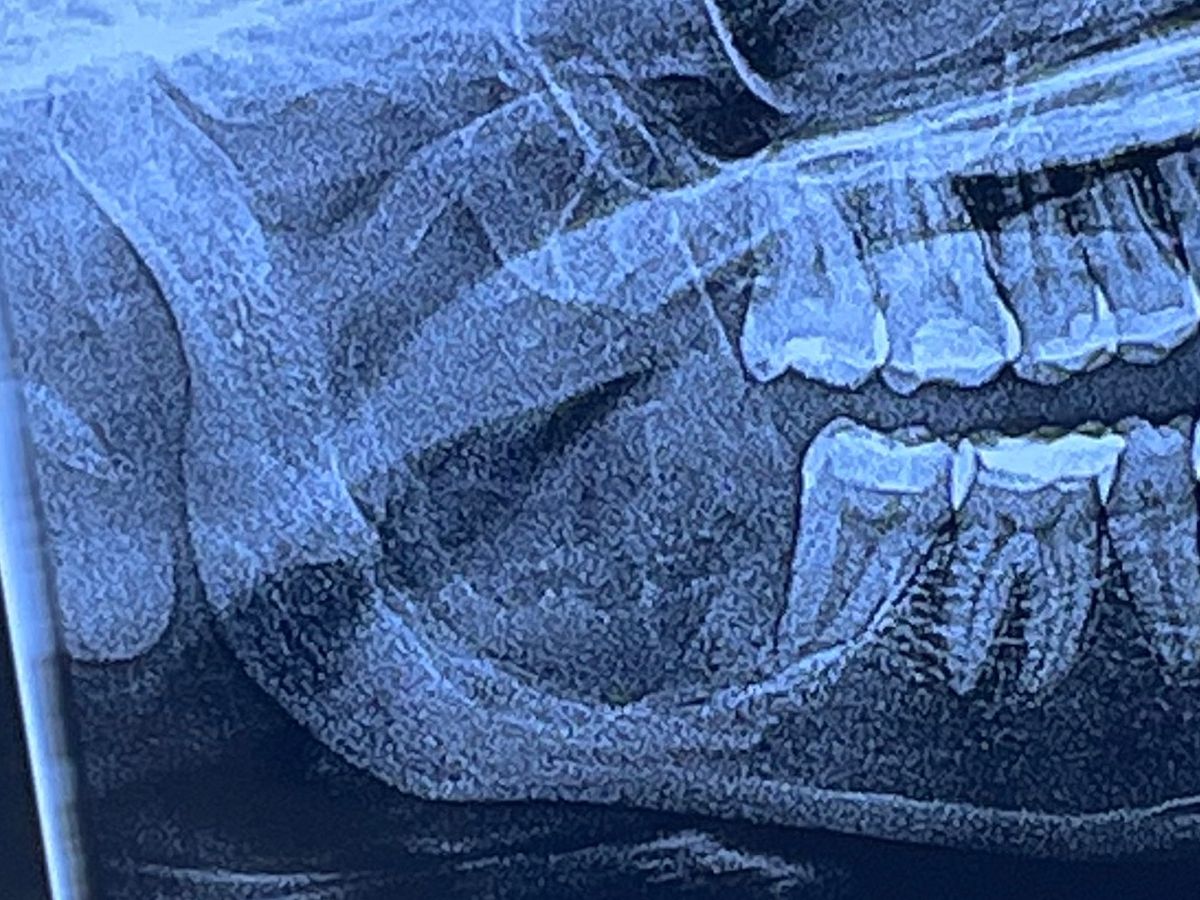

Hi, my name is Janessa, and I’m fundraising for a surgery I need to remove a Ameloblastoma I have in my right jaw. It’s hard for me to afford the surgery. The bone of my jaw on the right side where the tumor is needs to be completely removed and replaced with titanium plates and I also need complete nerve reconstruction. I will lose complete feeling in my bottom lip forever but it’s a sacrifice that has to be made. I need help to be able to afford the surgery. Any donation will be greatly appreciated!